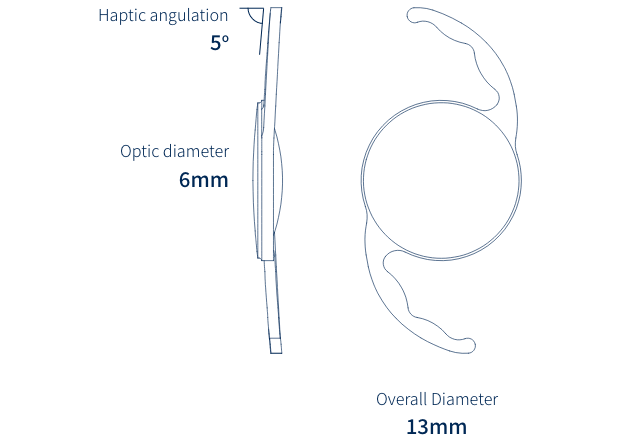

SeeLens

SeeLens